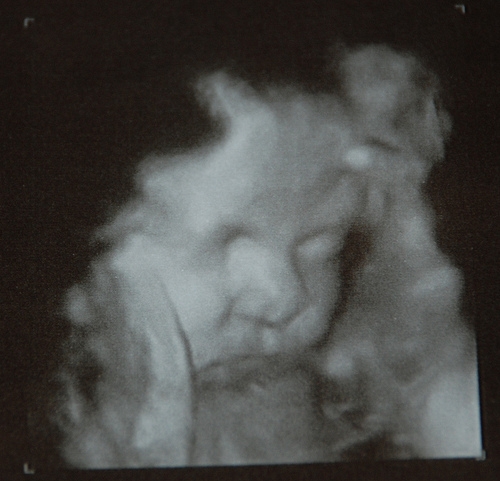

Фотографии, полученные во время УЗИ на 42 неделе, могут показать, как выглядит плод в этот период. Обычно на изображениях можно увидеть хорошо сформированные черты лица, конечности и другие анатомические детали. Эти изображения могут стать ценным воспоминанием для родителей, ожидающих встречи с малышом.